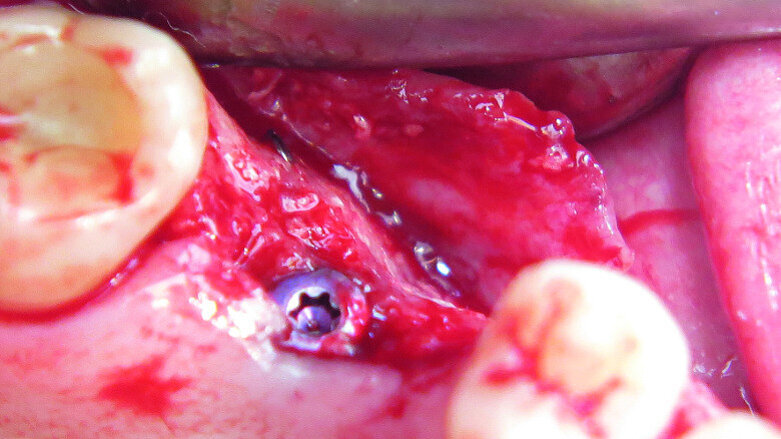

Fig. 2: Micro-osteoperforation in order to enhance bone formation.

The first was a 51-year-old patient who smoked 30 cigarettes per day and suffered from diabetes and stress (Figs. 1–8). The second was a 76-year-old male patient in good physical condition who smoked 40 cigarettes per day. He underwent reconstruction of the premaxilla (Figs. 9–13). The third was a healthy female patient of 24 years of age who smoked 20 cigarettes per day. She required a sinus lift in region #25 (Figs. 14–21). The patients were informed of the intended process in detail and signed the surgical protocol containing information concerning possible risks of failure and complications, as well as information on the alloplastic and synthetic materials to be used.